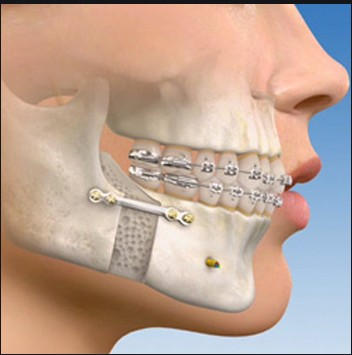

- Orthognathic surgery is also known as corrective jaw surgery

Is a surgery designed to correct conditions of the jaw and face related to

Structure, Growth, Sleep Apnea, TMJ disorders, Malocclusion problems owing to

skeletal disharmonies, or other orthodontic problems which cannot be easily treated

with braces.

This surgery is also used to treat congenital conditions such as cleft palate

The main goals of orthognathic surgery are to achieve a Correct bite, an Aesthetic

face, and an Enlarged airway for easy breathing.